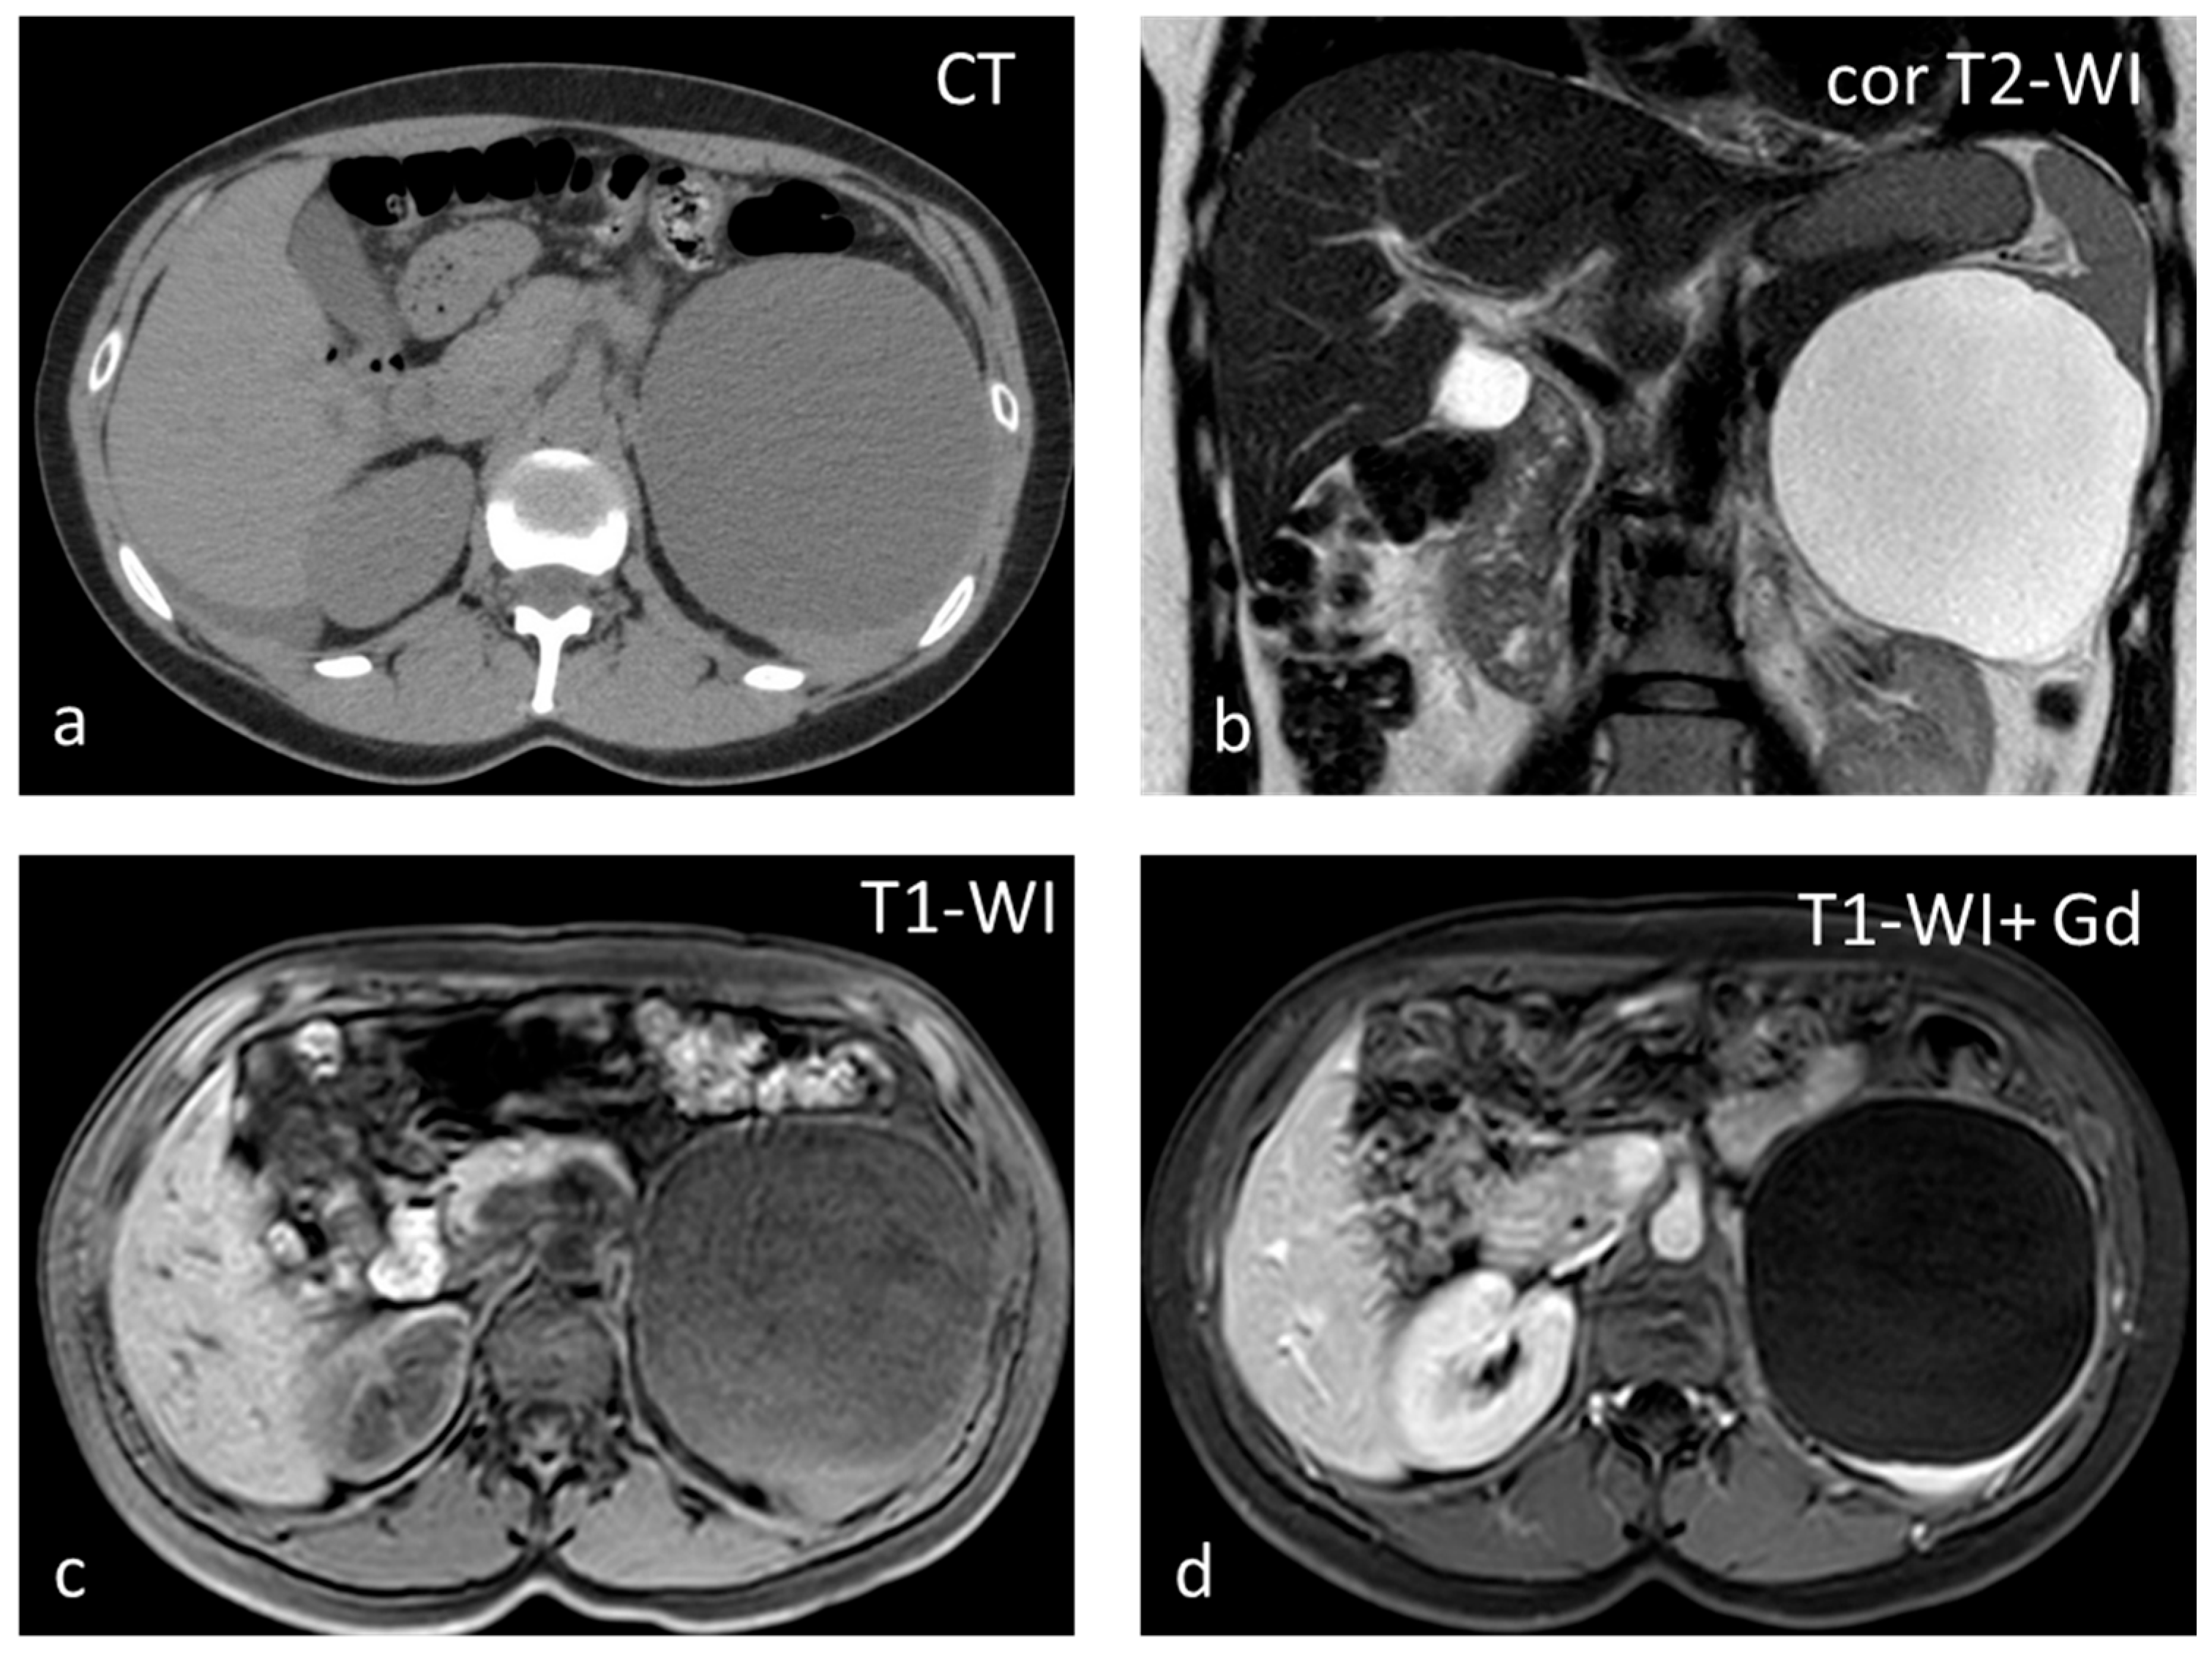

Cysts, most often solitary, are usually incidental findings, being asymptomatic [25]. Two categories exist: primary (true) and secondary (false). Primary cysts, also called epidermoid cysts, are congenital lesions with an epithelial lining, with a 20% prevalence in females. Possible explanations for the pathogenesis of true cyst include (1) infolding of peritoneal mesothelium after rupture of the splenic capsule, (2) collections of peritoneal mesothelial cells trapped in splenic sulci, or (3) origin from normal lymph spaces [27]. Primary splenic cysts constitute 10% of all nonparasitic cysts of the spleen. It is a rare condition with an incidence rate of 0.07%, as reported in a review of 42,327 autopsies [28]. Secondary cysts are lined by a fibrous wall and most often are post-traumatic. Rarely they may occur in splenic abscess or splenic infarction [29]. At ultrasound (US), cysts appear as well-defined rounded lesions with a thin wall and anechoic fluid content. They appear homogeneously hypoattenuating on CT and lack enhancement. Calcifications may be seen in the wall in post-traumatic cysts. Unless hemorrhage or debris is present, at MRI, splenic cysts appear hypointense on T1-WI and homogeneously hyperintense on T2-WI (Figure 4). Simple cysts, either primary or secondary, do not warrant further follow-up with imaging. However, due to the increased risk of complications (rupture, infection, hemorrhage), splenic cysts larger than 5 cm or symptomatic ones should be treated surgically, trying to preserve as much of the splenic parenchyma as possible [30].

Figure 4.

Large splenic cyst appearing homogeneously hypodense on non-contrast CT (a). The cyst content is homogeneously hyperintense on T2-WI (b) and hypointense on T1-WI (c). The cyst wall does not show significant enhancement (d).